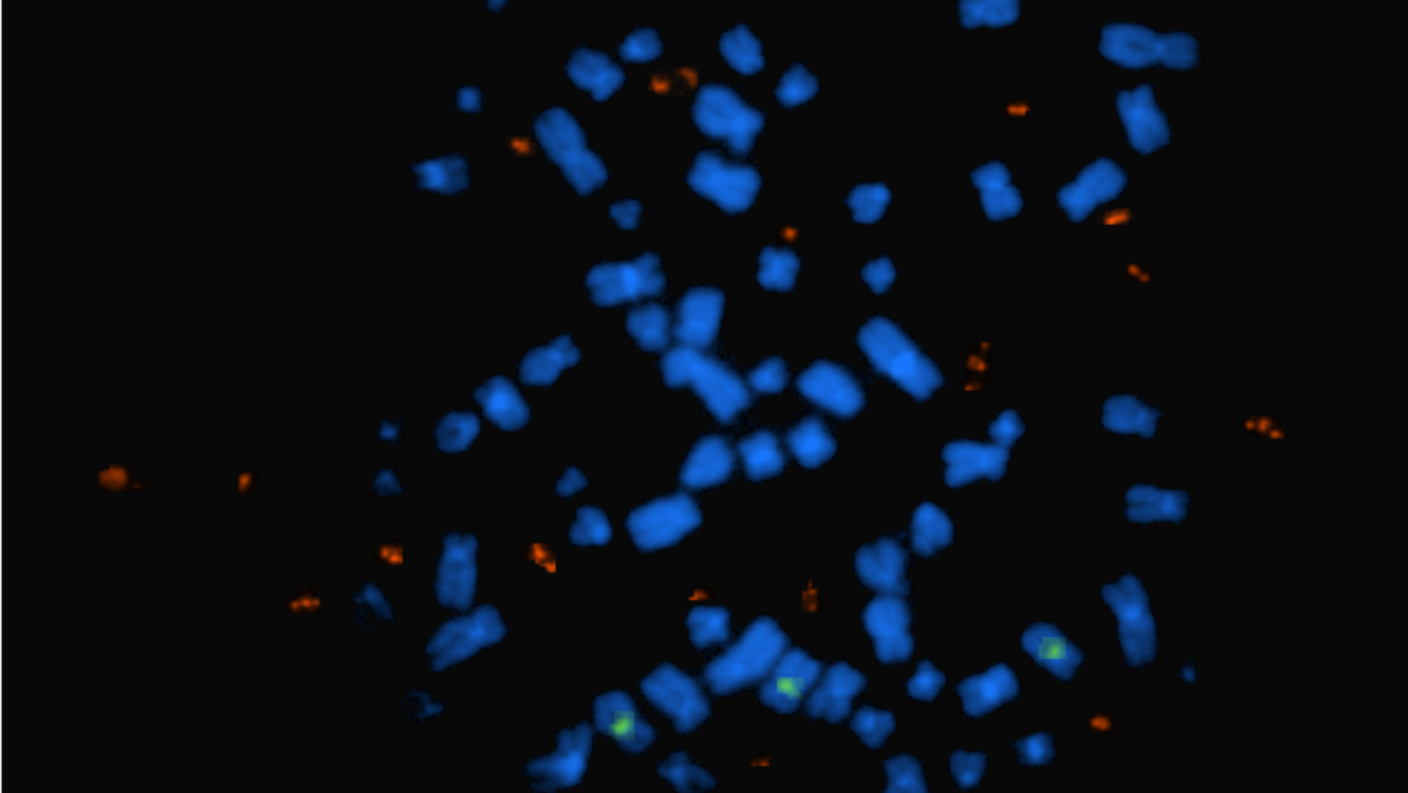

Overall, about 2.5% of glioblastoma cells from the samples tested expressed THBS1, and cells from areas with high functional connectivity had higher levels of THBS1 expression than areas with low functional connectivity. Microscopy techniques confirmed that a subgroup of tumor cells in areas with high connectivity produced TSP-1, and that these areas formed more new synapses.

When the researchers grew neurons and tumor cells taken from either high connectivity or low connectivity areas together in lab dishes, tumor cells from high connectivity areas boosted the formation of new synapses and formed synapses with neurons themselves.

In contrast, tumor cells from areas with low connectivity did neither. But when the researchers added TSP-1, these tumor cells and neurons suddenly started to form connections.